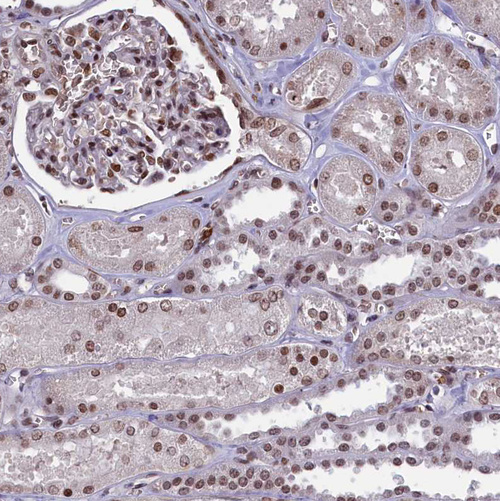

Immunohistochemical staining of human cerebral cortex, endometrium, kidney and testis using Anti-MPHOSPH8 antibody HPA040035 (A) shows similar protein distribution across tissues to independent antibody HPA039701 (B).